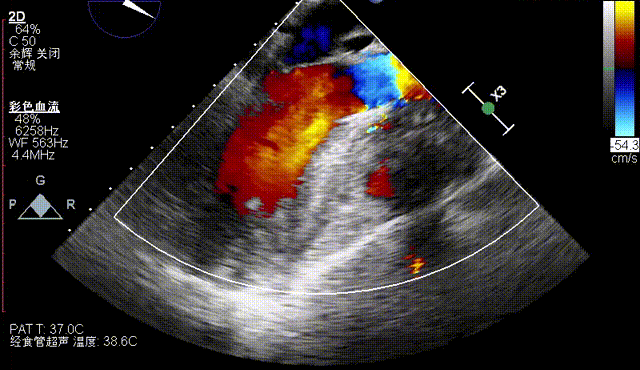

术后即刻评估

术后即刻TEE示主动面瓣膜最大峰值血流速为2.1 m/s,平均跨瓣压差为8.6 mmHg,少量瓣周漏。

术后即刻TEE示主动面瓣膜最大峰值血流速为1.1m/s,平均跨瓣压差为2mmHg,少量瓣周漏。